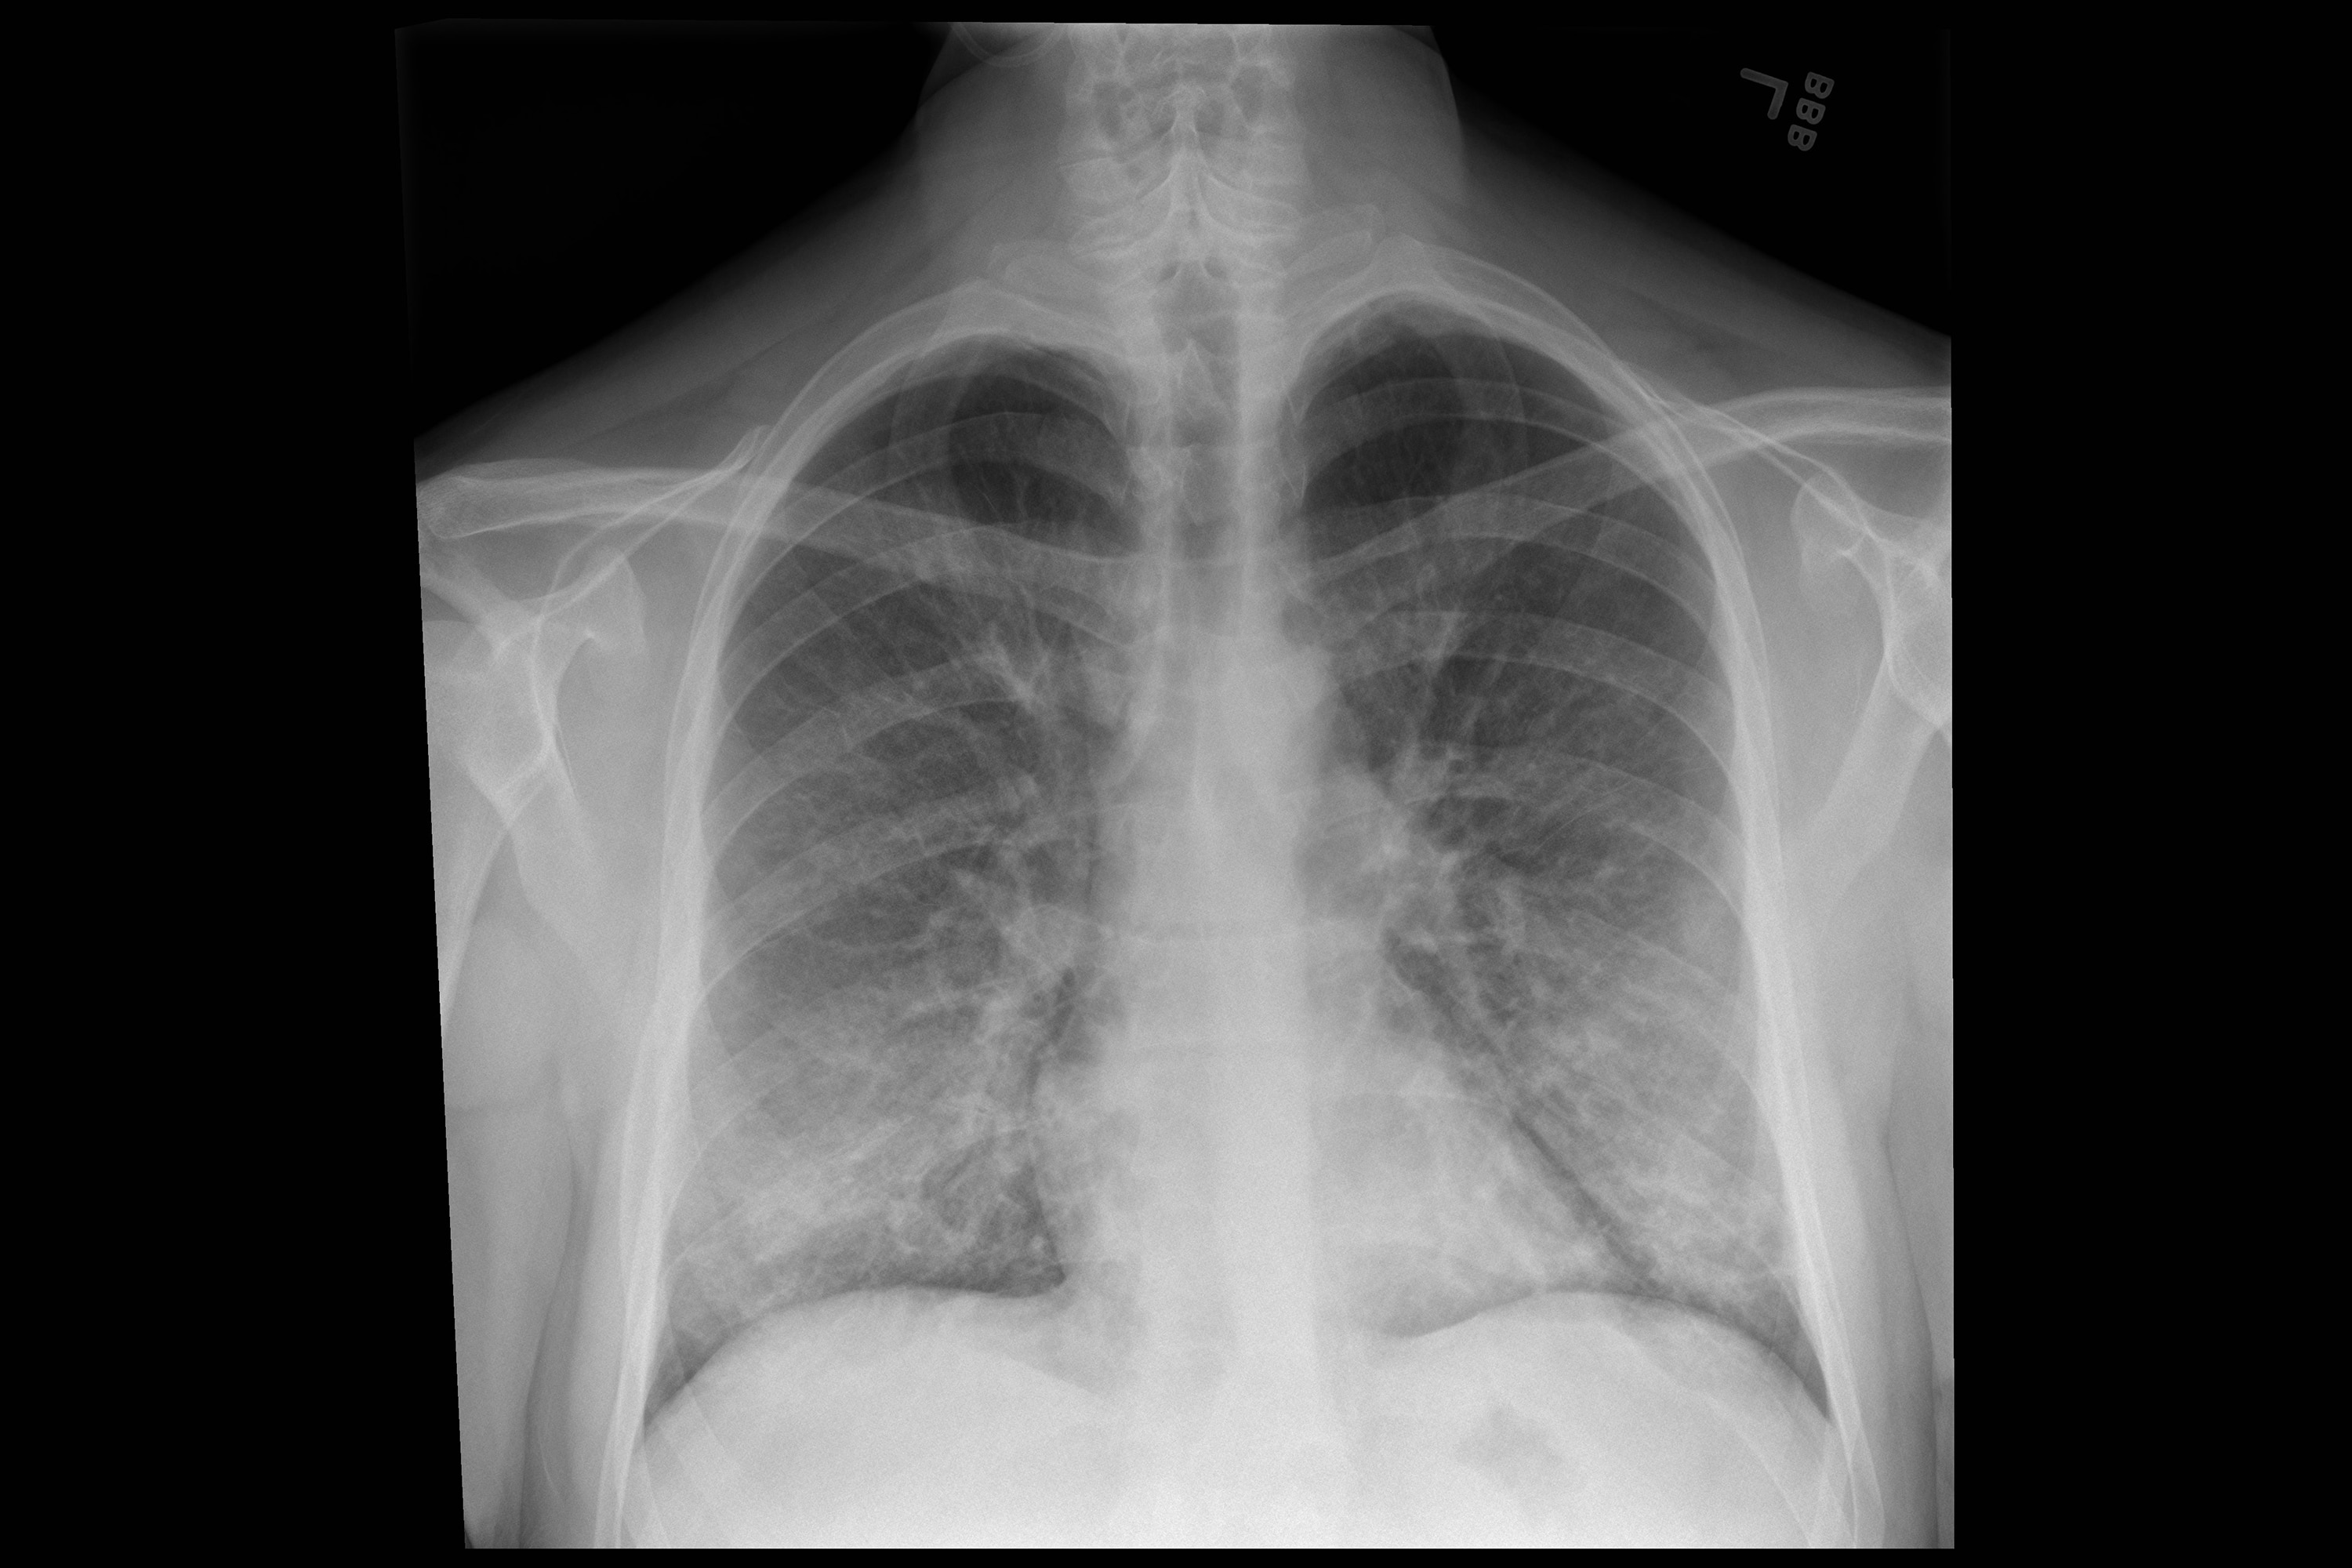

27+ Chest And Lung Pain After Vomiting UK. So 2 nights ago i vomited after eating way too much over the weekend.( i rarely vomit) it was pretty rough and took a lot out of me. The cough caused some of the worst chest pain i've ever experienced and it was.

Reasons can include digestive and abdominal issues this article will explore the potential causes of chest pain and vomiting. It can be fatal, sometimes even within minutes. Vomiting after a full meal. Nausea and vomiting from general anesthesia.